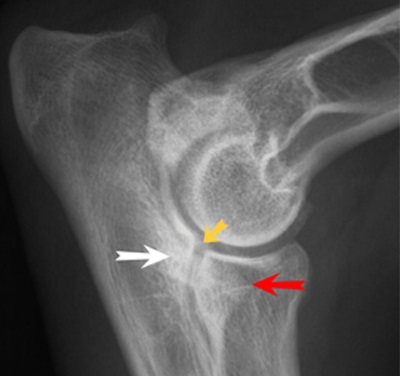

A betegség diagnózisa alapján röntgen vizsgálat. Képek diszplázia könyökízület fut egy egyenes vonal craniocaudalis és oldalvetületbe lateromedialnoy egyidejűleg a képeket a csípő, amikor eléri a 12 hónapos kor. a kis- és közepes méretű fajták és 18 hónap. A nagy és óriás fajták.

Az oldalirányú kiemelkedés mellső láb kell hajlítani a könyök szögben 36-45 °. Ilyen helyzet lehetővé teszi, hogy láthatóvá tegyük a folyamatok minimális zavaró árnyékok.

A - ás porcszövet eredetű exostosisok (kinövések) a condylus humerus;

B - exostosisok a kampó alakú nyúlvány;

B - a porc melletti sclerosis a ker. Vágás után blokk;

G - exostosisok a cranialis része a sugár.